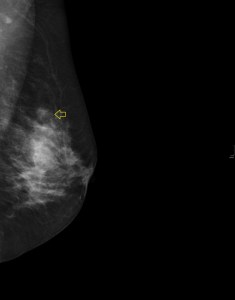

En el caso que te presento hoy, una mujer, que se realiza una revisión ecográfica mamaria por seguimiento de una lesión nodular en la mama izquierda a expensas de una mamografía, imagen 1, donde se observa en cuadrantes superiores una lesión nodular marcada con flecha amarilla.

Cuando realizamos la ecografía objetivamos un nódulo en la región donde teóricamente tendría que estar el nódulo visualizado en la mamografía. Hasta aquí todo genial, el problema es que las dimensiones del nódulo de la mamografía y el de la ecografía son demasiado diferentes y por tanto no concordantes.

La paciente tiene una mancha en la línea intercuadrántica externa de la mama a estudio, coincide en tamaño y posición con el nódulo mamario. Normalmente las lesiones cutáneas objetivadas en mamografía son debido a verrugas o lunares voluminosos, en este caso la casualidad hizo coincidir un nódulo en la mama con la misma localización (imagen 2) de una lesión cutánea que, normalmente no vemos con el estudio ecográfico, pero esta, por su profundidad me llamó la atención y la radióloga recomendó estudio por parte del servicio de dermatología del hospital para caracterización.

1

Si te fijas en la imagen, la lesión mamaria es un nódulo evaluado por la radióloga con aspecto de benignidad, redondeado, buena transmisión de sonido, bordes bien definidos.